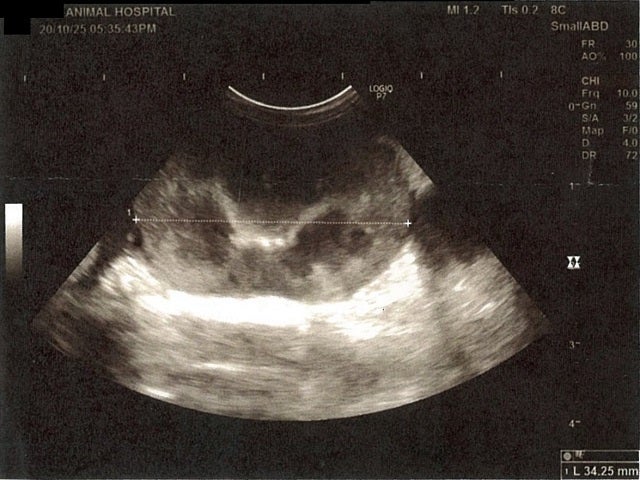

左腎臓周りに腹水が確認できるエコー写真

《心臓周りの胸部以外の全ての腹部で腹水がみられるとの診断です》

大網という部分で内臓を包む膜のようなものです。その周りに腹水が溜まっています。